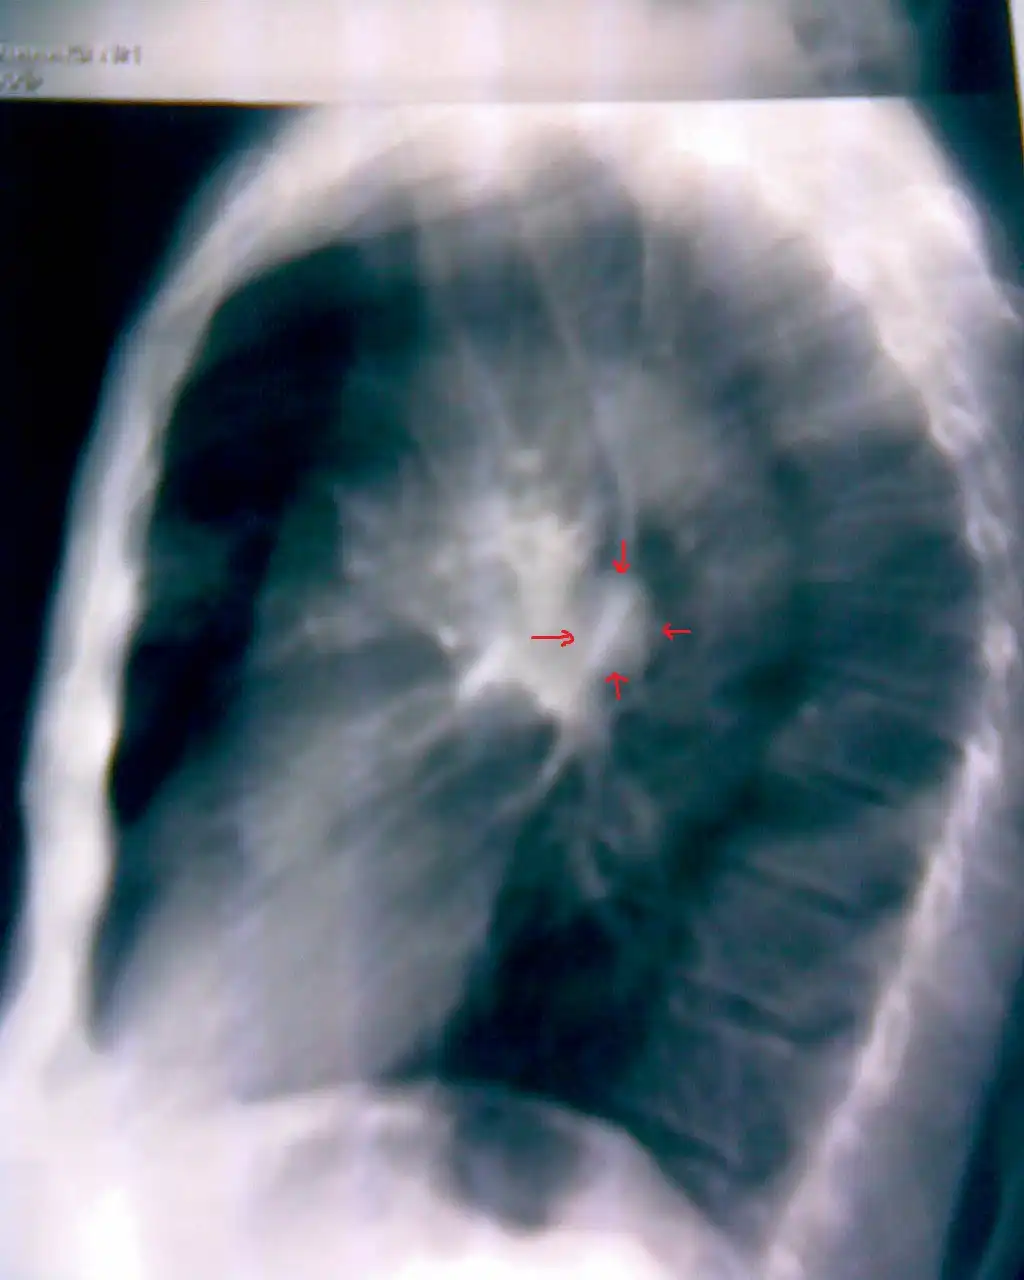

Линейная томограмма: